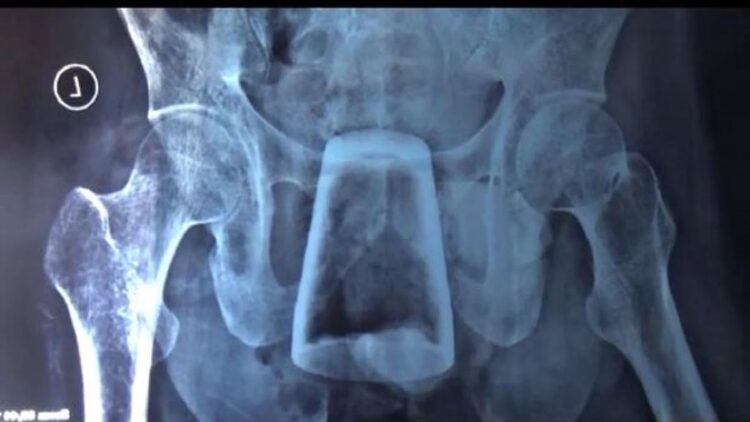

Hasil rontgen yang diungkap para dokter menunjukkan gelas tersebut ada di rektum, yakni bagian akhir usus besar yang dekat sekali dengan usus. Dugaan paling logis menurut kedokteran, benda tersebut dimasukkan sendiri oleh pasien.